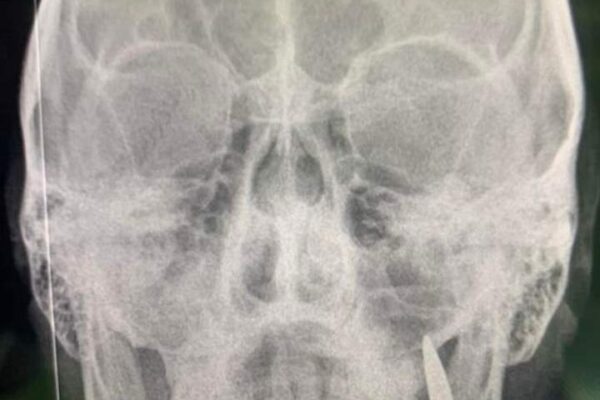

Лікарі стабілізаційного пункту поблизу передової виявили у щелепі пораненого бійця замість зубів кулю.